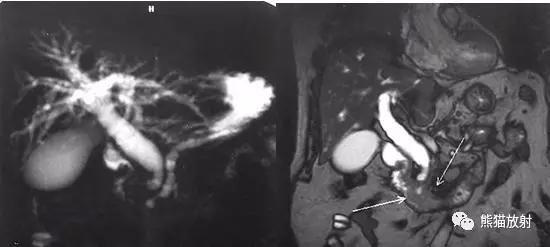

- 磁共振胰胆管造影(MRCP)

采用重T2加权序列(TE>160ms)兼用脂肪抑制技术,以三维模式连续扫描多个(有时层间重叠)薄层原始图像。MRCP和MRU检查时通常在自由呼吸过程中由呼吸门控触发采集。扫描结束后在工作站对原始图像进行后处理,以最大信号强度投影(MIP)重组,形成不同角度的多幅MRCP或MRU,即三维立体图像。

三维模式(即整体或容积形式)采集形成的水成像有两种图像,即薄层原始图像(层厚2~3mm)和MIP投影图像。

优点:扫描范围大,可在薄层原始图像观察细小病变,MIP图像显示的解剖结构层次丰富,信息量大,重组时可任意旋转方向和角度以进行最佳观察,可剪切掉多余的高信号结构(胃肠液体、肾囊肿等),避免解剖重叠。